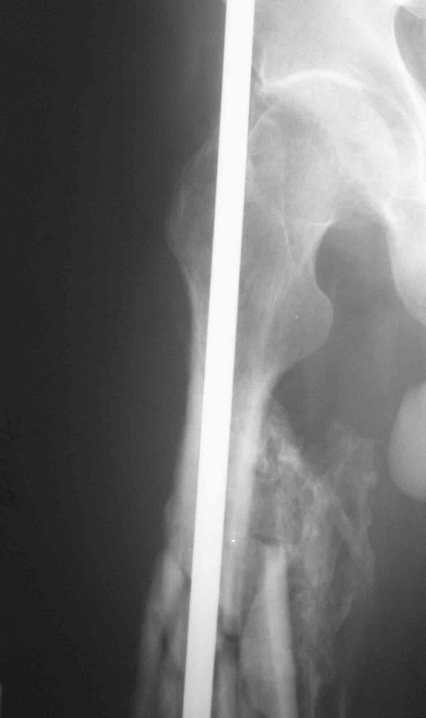

[Ortho] 32- летний пациент с переломами обоих бедер после неудачного оперативного и консервативного лечения.

Имя     : Fem L.jpg